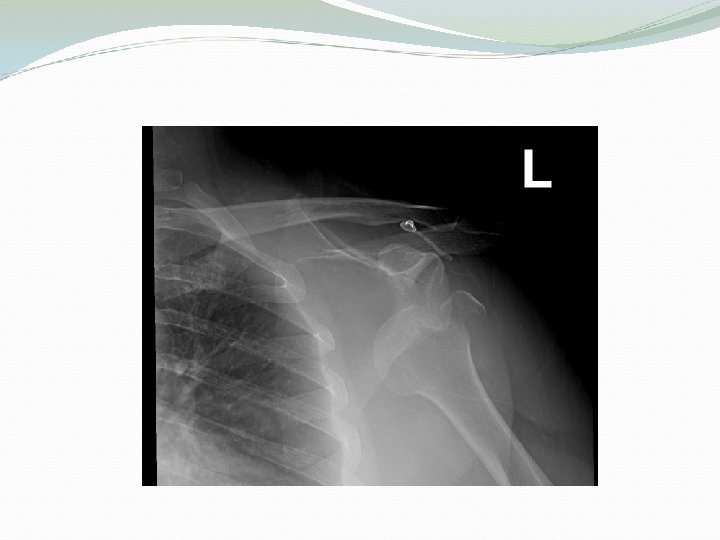

Associated injuries of anterior Shoulder Dislocation Injury to the neuro vascular bundle in axilla Injury of the Axillary Nerve ( Usually stretching leading to temporary neuropraxia ) Associated fracture

Complications of anterior Shoulder Dislocation : Early Neuro vascular injury ( rare ) Axillary nerve injury Associated Fracture of neck of humerus or greater or lesser tuberosities